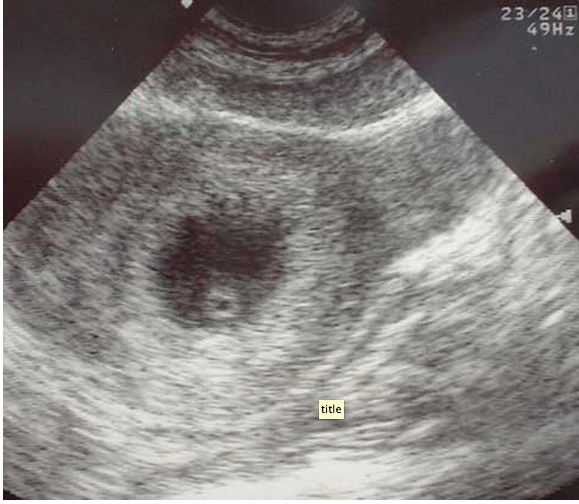

“You arrive to the emergency department for your first night shift of the month, and as you place your bag on the desk, the attending walks towards you with a chart in his hand. “Do you mind seeing this patient? It’s a COPD’er with dyspnea. It’s probably just a COPD exacerbation.” You look at the chart and see that it’s a 46 year old female with shortness of breath. As you walk into the room, you notice the patient appears slightly pale, is afebrile, has an O2 saturation of 91% and is tachycardic in the 110’s with a blood pressure of 105/76, temperature of 98.5° and respiratory rate of 26. While taking the history, you note that the patient is a smoker and recently returned from a 12 hour car ride to see relatives. Suspecting that this may be something other than simple COPD exacerbation, you grab your ultrasound machine and start with the cardiac echo (as described in the RADiUS protocol) and are able to get the following image:

This apical 4-chamber view shows severe right heart dilation, defined as a RV:LV ratio >1. However, you remember that the patient has a history of COPD, and chronic pulmonary hypertension can cause chronic right ventricular dilation1. At that moment, the patient becomes hypotensive with a systolic blood pressure in the 70’s and develops severe respiratory distress. What should we do?